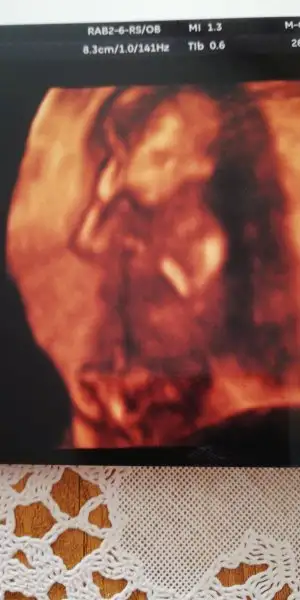

Bebeğin 4 boyutlu Görüntüsünde yüzünü göstermeye çalıştı beni mutlu etmek için ama kuzucuk bir dönmedi yüzünü :) öksürmemi istedi Dr öksürünce hareket ediyormuş cidden öyle :)

Bebiş sat ta 15+6 141 grnormalmiş